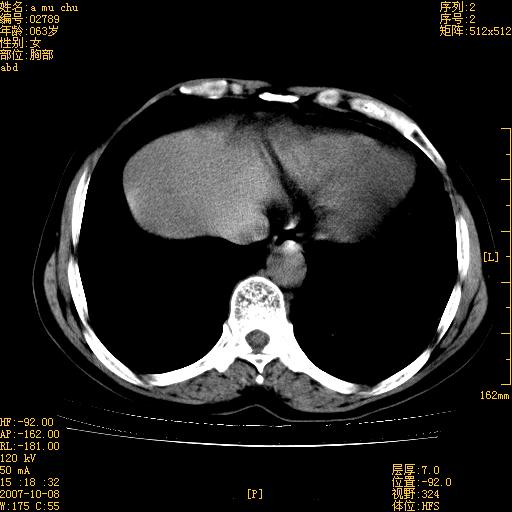

以下是引用王维浦在2007-10-17 21:02:00的发言:[br]胆囊增大,囊壁明显不规则增厚,邻近肝组织浸润,肝内外胆管无扩张。诊断:胆囊ca;[br]胰头软组织肿块影,考虑是由转移肿大的胰后淋巴结、没有肠道准备的十二指肠及胰头共同形成。[br]

以下是引用zhangzexing在2007-10-18 7:13:00的发言:[br]支持胰头占位,慢性胆囊炎. 2.肝左叶前外侧段占位,血管瘤?建议增强

以下是引用影像实习生在2007-10-17 19:49:00的发言:[br]支持胰头占位,慢性胆囊炎. 2.肝左叶前外侧段占位,血管瘤?建议增强.

以下是引用刘振江在2007-10-17 19:42:00的发言:[br]没有增强,胰头癌?胆囊及肝左叶占位?